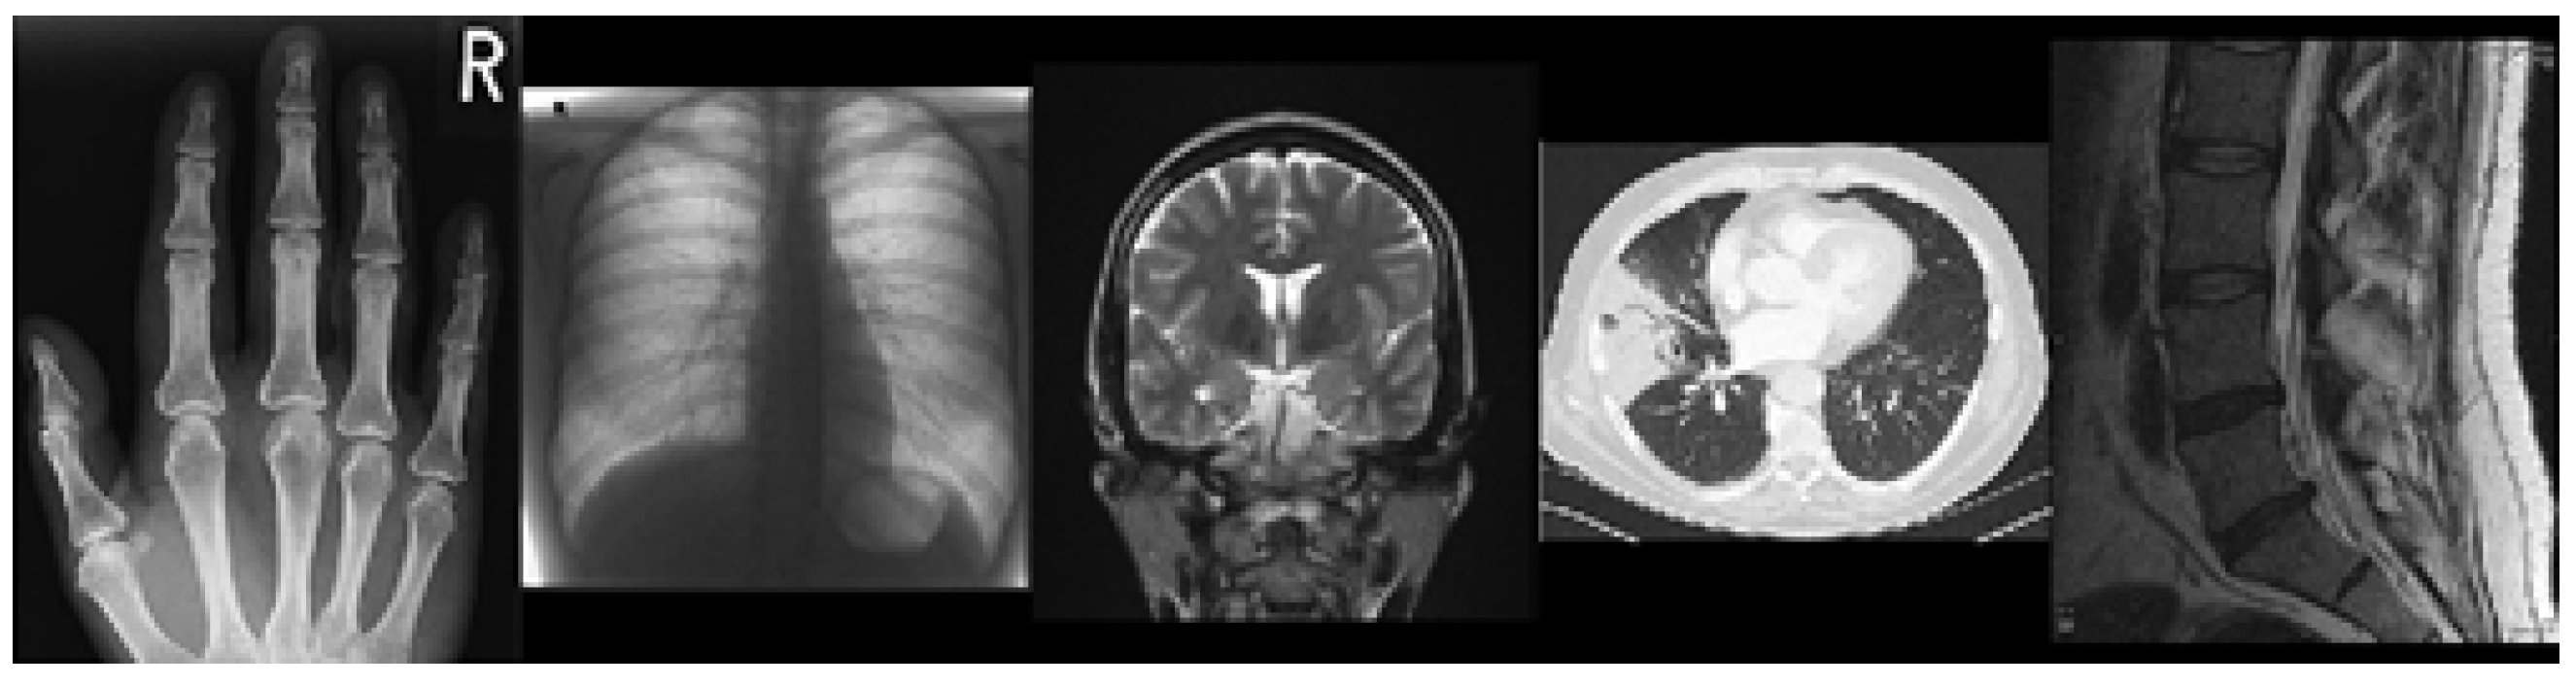

Figure 1 shows five public-domain images of “Mandrill”, “Bear”, “Camera”, “Chilies”, and “Humming bird” obtained from https://commons.wikimedia.org/ (accessed on 11 March 2024). Figure 2 shows the blurry images after the original image is noised.

Figure 1. Original images [36].

Mathematics 12 02360 g001

In order to better validate the proposed method, we conducted experiments on several public-domain medical images obtained from https://commons.wikimedia.org/ (accessed on 11 March 2024). Figure 4 shows the original medical images of “Heart” and “Spleen” from the MSD dataset. Figure 5 shows the blurry images after the original images were noised.

Figure 4. Original images [36].

Mathematics 12 02360 g004